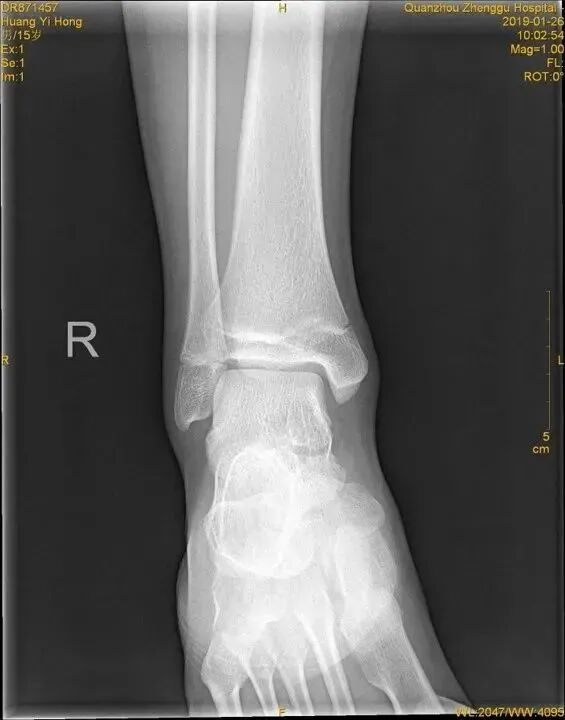

外旋位扭伤受伤时距骨受到外旋外力,或小腿内旋距骨受到相对外旋外力。随着外旋暴力增大下胫腓联合主要韧带断裂,下胫腓联合分离。严重的多合并外踝骨折或内侧韧带断裂。